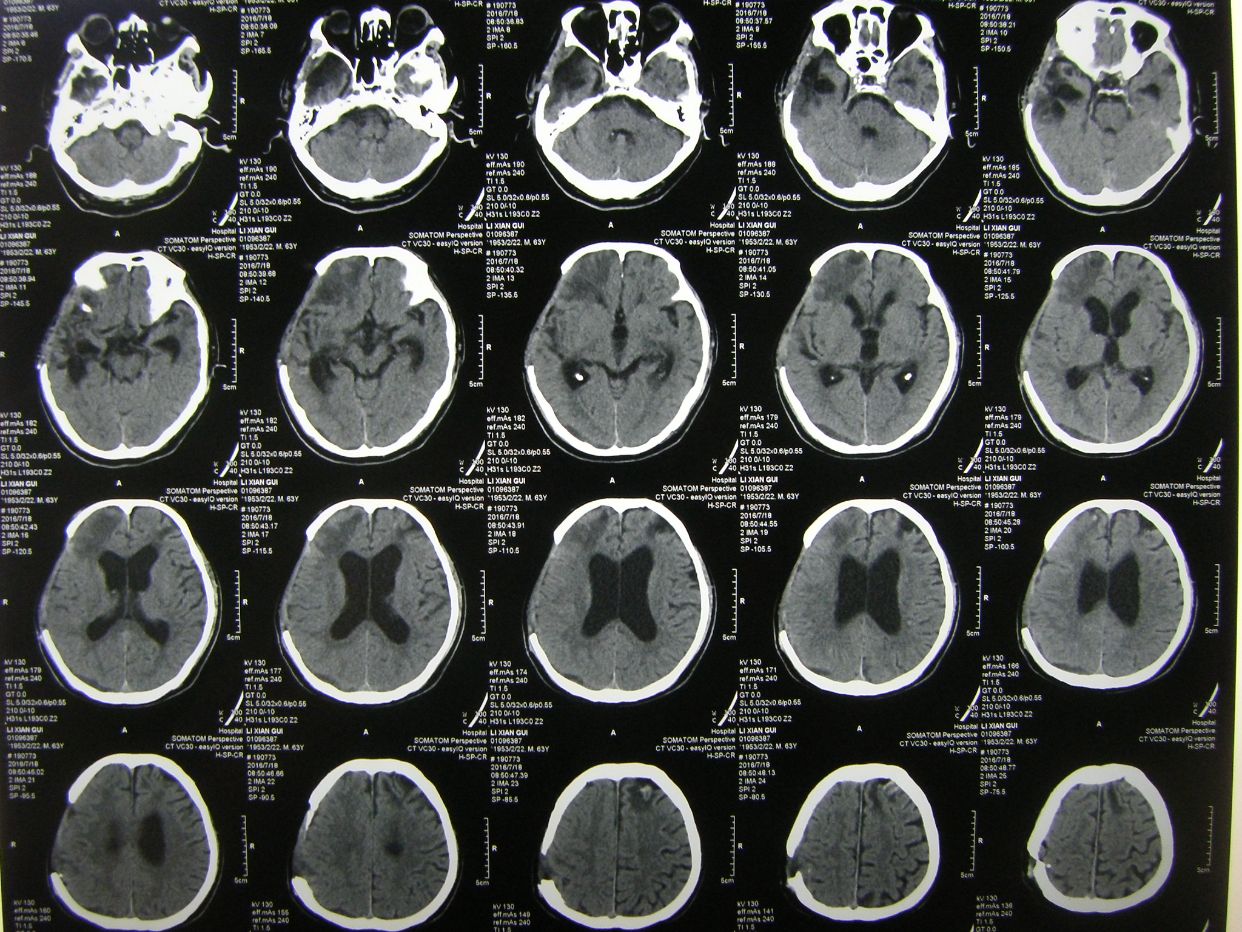

例1,男,61岁,言语不清伴左侧肢体活动障碍1小时入院。

CT示右基底节区脑出血,占位明显,中线移位。因出现右侧瞳孔增大,急症全麻下开颅血肿清除去骨瓣减压。

术后1天CT复查,血肿清除满意,中线恢复。

术后半月CT复查示,水肿基本消退,脑室无扩大。

例2,男,63岁,被发现卧倒在地意识不清半小时入院。

CT示右额颞顶大量硬膜下血肿,右额颞叶脑挫裂伤,中线明显移位。急症全麻下开颅,血肿清除去骨瓣减压术,及气管切开术。

术后CT复查示,血肿清除彻底,中线居中,额颞叶水肿期。

术后3周CT复查,脑水肿消退,中线居中。